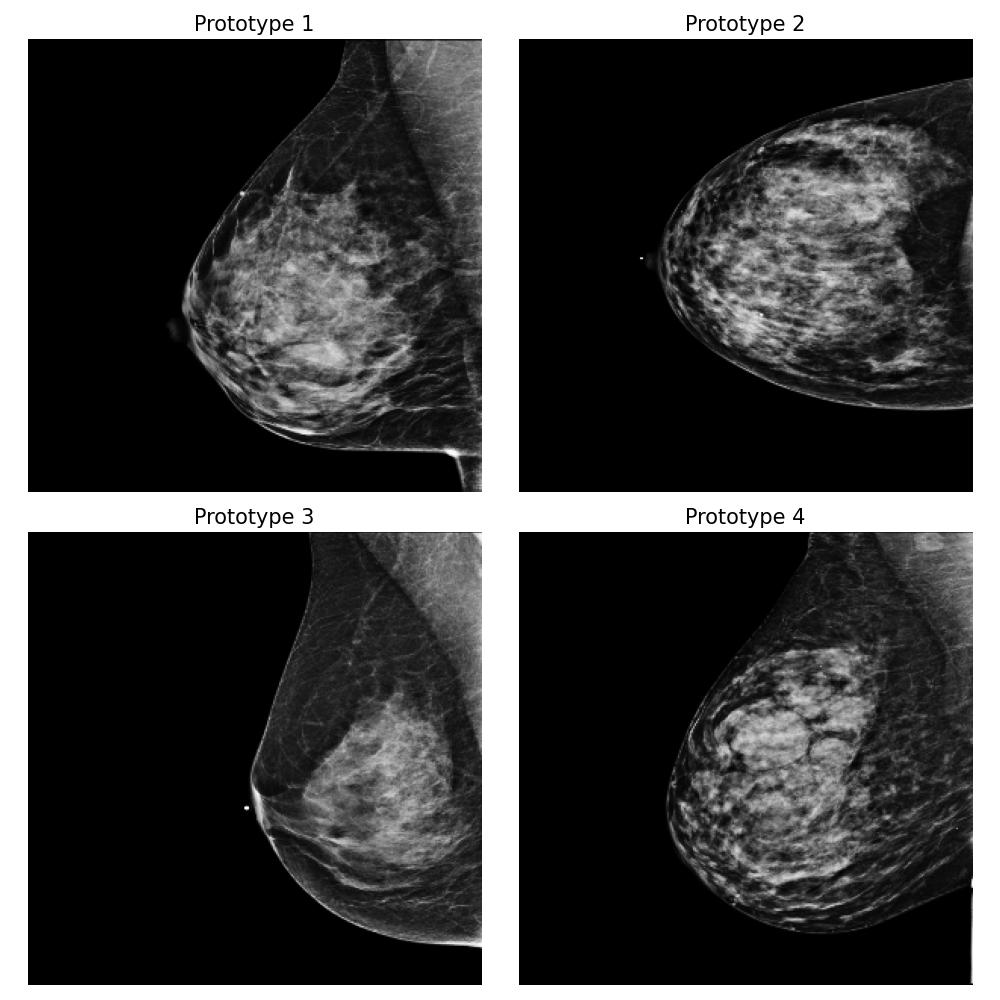

Dataset and

We use the publicly available EMBED dataset (Jeong et al., 2023). To simulate premenopausal and postmenopausal patient populations, we construct two datasets, and , by randomly sub-sampling from EMBED. Dataset comprises 27,224 mammograms from 8,456 patients with dense breast tissue (density category three in EMBED) and 21,675 mammograms from 7,841 patients in density category two. Dataset includes 27,224 mammograms from 2,715 patients with less dense tissue (density category one) and 21,675 mammograms from 7,797 patients in density category two (medium density). All mammograms were preprocessed to remove clinical markers and aligned such that the breast tissue faces left.

For this task, we implemented the “Prototype-summarization-based explanations” described in Section 3.5. We trained a binary vs classifier using the VGG19 feature extractor as backbone and learn four prototypes for each dataset. 97798 mammograms were used for training, and 24450 mammograms were used for testing.

Result

By examining the summarization prototypes shown in Figure 22, we identified tissue density as the primary difference between and . In mammograms, brighter areas correspond to denser tissue. Additionally, we observed that less dense tissue is often associated with larger tissue size. Without our proposed method, human users would need to manually analyze the dataset, which is a labor-intensive and time-consuming task, to reach the same conclusions.

Robustness of the explanation

To examine the robustness of our explanation result, we repeat the explanation algorithm approach on bootstrapped versions of and . Five bootstrapped datasets were constructed by resampling by patients with replacement. As shown in Figure 35 in Appendix Section B.5, we reach the same conclusion for all the bootstrapped datasets.

Coverage evaluation

We again evaluate the coverage quality of the learned set of prototypes using the AUCC score. The coverage curve is shown in Figure 24. We also display the learned latent space for and in Figure 24 and the two datasets and the prototypes are well separated even though they contain overlapping mammograms with density category two (i.e. medium density breasts).